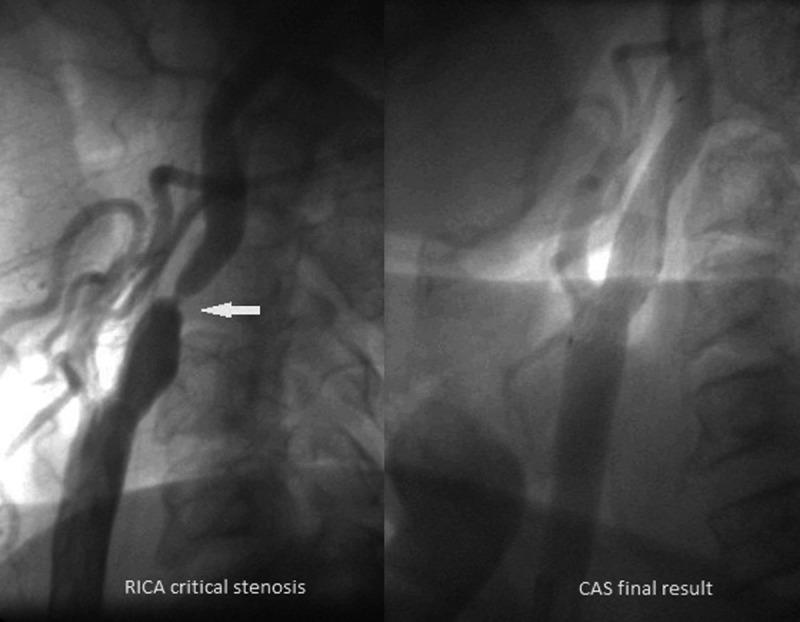

Coexistent carotid artery stenosis (CS) and multivessel coronary artery disease (CAD) is not infrequent. One in 5 patients with multivessel CAD has a severe CS, and CAD incidence reaches 80% in those referred for carotid revascularization. We reviewed treatment strategies for concomitant severe CS and CAD. We performed a literature search (MEDLINE) with terms including carotid artery stenting (CAS), coronary artery bypass grafting (CABG), carotid endarterectomy (CEA), stroke, and myocardial infarction (MI). The main therapeutic option for CS-CAD has been (simultaneous or staged) CEA-CABG. This, however, is associated with a high risk of MI (in those with CEA prior to CABG) or stroke (CABG prior to CEA), and the cumulative major adverse event rate (MAE - death, stroke or MI) reaches 10-12%. With increasing adoption of CAS, a sequential strategy of CAS followed by CABG has emerged. Registries (usually single-centre) indicate an MAE rate of ≈7% for CAS followed by CABG (frequently after >30 days, due to double antiplatelet therapy). Recently, 1-stage CAS-CABG has been introduced. This involves different antiplatelet regimens and, in some centers, preferred off-pump CABG, with a cumulative MAE of 1.4-4.5%. No randomized trial comparing different treatment strategies in CS-CAD has been conducted, and thus far reported series are prone to selection/reporting bias. In addition to the established surgical treatment (CEA-CABG, sequential/simultaneous), hybrid revascularization (CAS-CABG) is emerging as a viable therapeutic option. Larger, preferably multi-centre, studies are required before this can become widely applied.

同时存在颈动脉狭窄(CS)和多支冠状动脉疾病(CAD)并不罕见。5 分之一的多支 CAD 患者存在严重的 CS,而在那些需要进行颈动脉血运重建的患者中,CAD 的发生率达到 80%。我们回顾了同时存在严重 CS 和 CAD 的治疗策略。我们使用颈动脉支架置入术(CAS)、冠状动脉旁路移植术(CABG)、颈动脉内膜切除术(CEA)、中风和心肌梗死(MI)等术语进行了文献检索(MEDLINE)。CS-CAD 的主要治疗选择一直是(同期或分期)CEA-CABG。然而,这与 MI(在 CEA 之前进行 CABG 的患者中)或中风(在 CABG 之前进行 CEA 的患者中)的高风险相关,累积主要不良事件率(MAE-死亡、中风或 MI)达到 10-12%。随着 CAS 的广泛应用,出现了 CAS 后序贯 CABG 的策略。登记处(通常为单中心)表明,CAS 后序贯 CABG 的 MAE 率约为 7%(由于双联抗血小板治疗,通常在 30 天后进行)。最近,引入了 1 期 CAS-CABG。这涉及不同的抗血小板治疗方案,在一些中心,更倾向于非体外循环 CABG,累积 MAE 为 1.4-4.5%。目前尚未进行比较 CS-CAD 不同治疗策略的随机试验,到目前为止,报告的系列研究容易受到选择/报告偏倚的影响。除了既定的手术治疗(CEA-CABG、同期/序贯)之外,杂交血运重建(CAS-CABG)正在成为一种可行的治疗选择。在广泛应用之前,需要进行更大的、最好是多中心的研究。